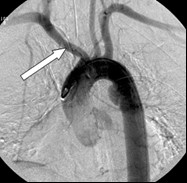

Na obrazie cyfrowej angiografii subtrakcyjnej strzałką zaznaczono

A. pień ramienno-głowowy.

B. żyłę płucną górną prawą.

C. pień płucny.

D. tętnicę szyjną wspólną prawą.